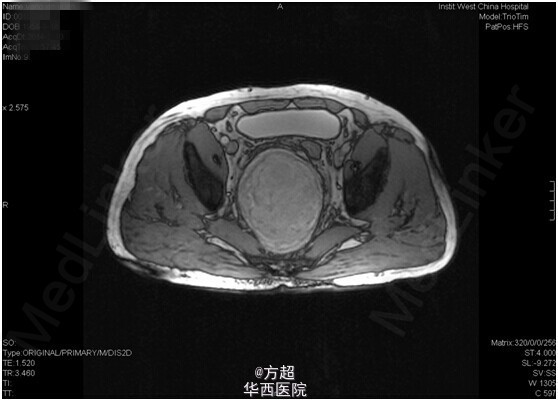

分享临床病例:盆腔巨大神经鞘瘤;中年男性,右下肢麻木、疼痛,大便习惯改变就诊,CT、MRI考虑盆腔巨大神经鞘瘤,椎管来源可能,完善术前准备后完整切除,术后病理神经鞘瘤,术后6月时随访无异常。神经鞘瘤由周围神经的Schwann鞘(即神经鞘)所形成的良性肿瘤;盆腔腹膜后神经鞘瘤较为少见,但因早期无明显症状,常因继发肢体疼痛麻木,或结直肠受压大便性状改变而就诊发现,通常包膜完整,手术完整切除为首选方案,但容易复发,且无特异性药物治疗。